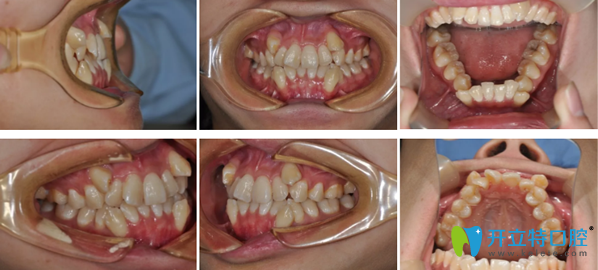

我矯正前牙齒的全方位照片:

鄭州拜博口腔牙齒矯正前

其實(shí),我的乳牙換完后,牙齒就不整齊,還有輕微的齙牙。但當(dāng)時(shí)家人也不重視。直到工作后,這一口錯(cuò)亂的牙齒給我?guī)砹撕芏嗖槐悖f話不自信,不敢張嘴大笑,說多了都是淚呀!

多余的話不說了。拜博口腔的雒云院長檢查后發(fā)現(xiàn),我的下頜牙列重度擁擠,上下頜雙尖牙偏牙弓頰側(cè)生長,雙側(cè)磨牙II類關(guān)系。這些都是專業(yè)術(shù)語,我也不太懂。我使用的是傳統(tǒng)金屬托槽矯正,價(jià)格實(shí)惠,正畸效果還好,不好的是矯正時(shí)間稍長。